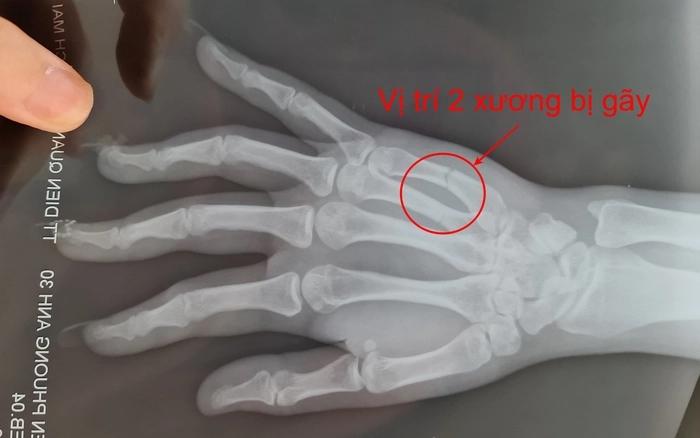

Hình chụp X-quang

"Thậm chí sau khi 2 bên đã tách nhau ra, trong lúc chồng tôi đang hỏi tôi về vấn đề sức khỏe bởi tôi chảy máu nhiều, nghi sảy thai thì bất ngờ chị K.A. và chồng rút hung khí tự chế trong nhà ra để đánh gia đình tôi. Thời điểm này có nhiều người dân chứng kiến xung quanh có thể làm chứng cho tôi, camera cũng có ghi lại", chị Phương Anh nói, đồng thời cho biết theo kết quả thăm khám, chị bị gãy 2 xương L4, L5 ở bàn tay trái và sảy thai.